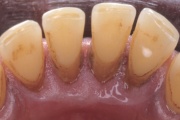

- igemed veritsevad (19)

- igemed punetavad (21)

- ige on paistes (mädapunn)

- igemed on tursunud/vohavad (17)

- puudulik suuhügieen (5)

- igemepealne hambakivi (5)

- igemealune hambakivi (4)